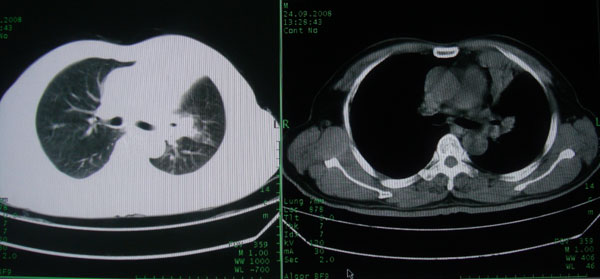

患者男性58岁因二周前起咳嗽,今天胸片示左上肺占位性病变行ct检查,无发热,无咯血痰.

左上肺感染性病变,结核伴空洞形成可能,左上肺膨胀不全

左肺上叶病灶,实变但见含气支气管、空洞但未见壁内结节及积液;

考虑:①感染性病变(包括特殊感染型肺tb)

②肿瘤性病变(考虑患者年龄比较大的关系/所以不排除)

初学者。。。左肺空洞性病变,并可见阻塞性肺不张改变,鉴于患者为老年男性,且临床症状仅有咳嗽,全身中毒症状不明显,所以我首先考虑为左肺癌性空洞并左侧肺门淋巴结转移伴左肺阻塞性肺不张。结核性空洞放于第二位考虑,可以进行相关实验室检查。希望能有病理结果,谢谢!!!!!

左肺上叶实变影,内见支气管充气征及空洞影,病人年龄较大,无发热及结核中毒症状,心影左移,未见纵隔淋巴结肿大;不知实验室检查结果如何?有否嗜酸细胞增多,有没有进行治疗?就目前资料首先考虑1.感染性病变,2.慢性嗜酸性肺炎?可结合实验室检查并短期治疗复查,肺癌不能排除。